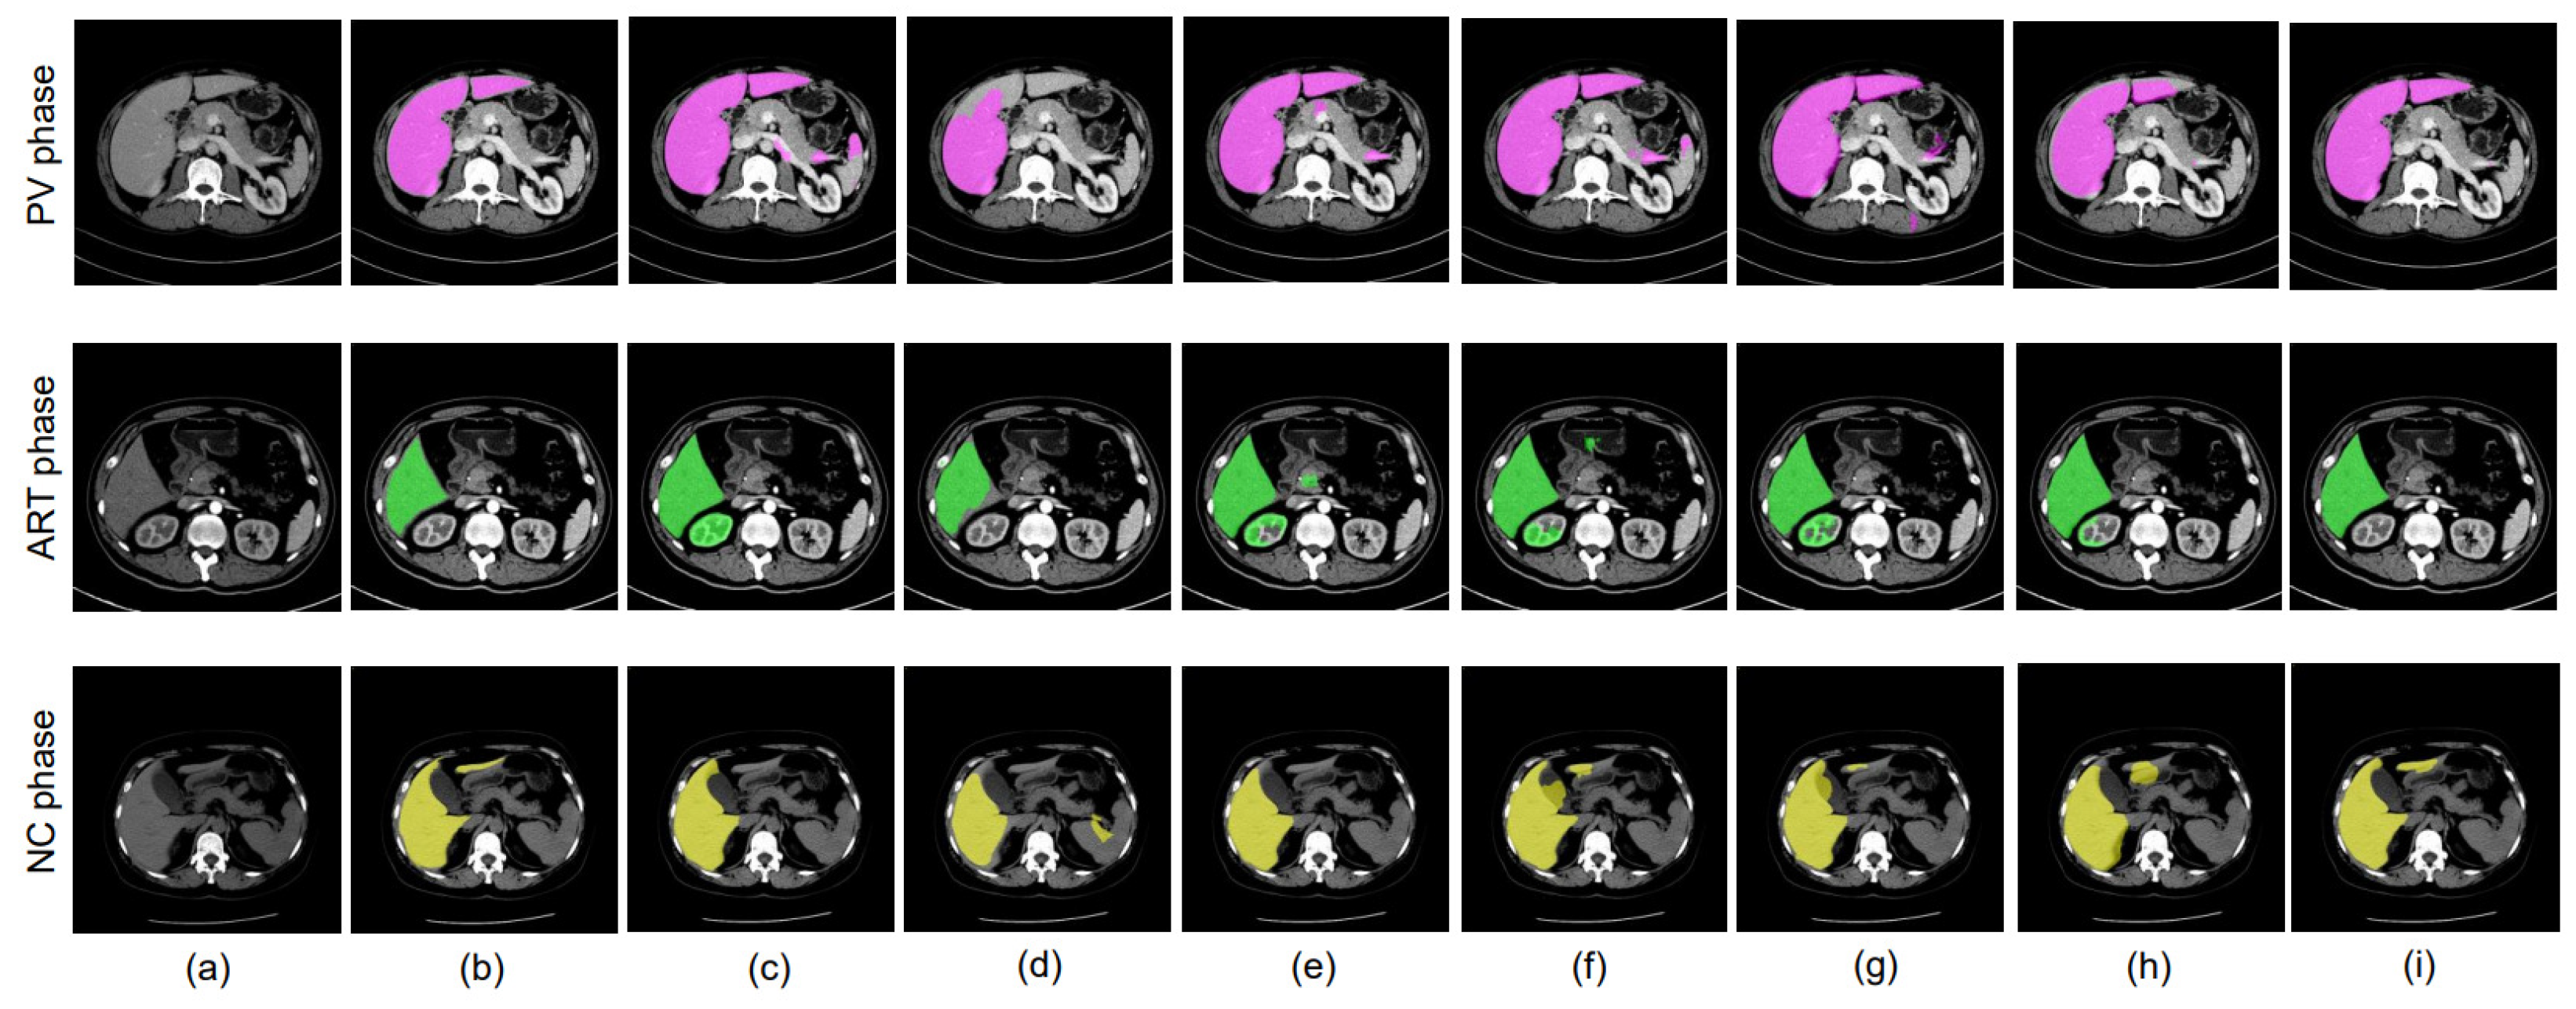

4.1. Dataset

4.2. Data Preprocessing